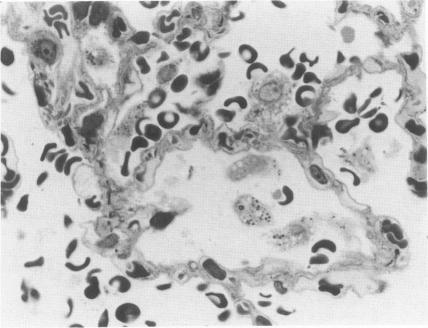

肿瘤坏死因子在IgA和IgG免疫复合物所致肺损伤发病机制中的不同作用

Contrasting roles for tumor necrosis factor in the pathogeneses of IgA and IgG immune complex lung injury.

Recent studies suggest that development of acute gamma G immunoglobulin (IgG) immune complex lung injury is partially dependent on a tumor necrosis factor (TNF)-dependent mechanisms of neutrophil (PMN) recruitment. The authors have sought to further define the role of intrapulmonary TNF in IgG alveolitis and to examine its role in IgA immune complex alveolitis, a neutrophil-independent model of acute lung injury. IgG immune complex lung injury resulted in a marked rise in intrapulmonary TNF activity accompanied by progressive pulmonary PMN accumulation. Intratracheal instillation of neutralizing concentrations of anti-TNF markedly reduced PMN influx measured at 4 hours but had no effect on PMN recruitment quantitated at 2 hours. IgA immune complex deposition resulted in acute lung injury accompanied by increased numbers of intrapulmonary mononuclear phagocytes but few neutrophils. Lung lavage fluids obtained from IgA immune complex-injured rats contained both neutrophil and monocyte chemotactic activities, albeit at twofold to fourfold lower concentrations than observed in IgG-mediated alveolitis. In contrast to IgG complex-mediated alveolitis, lung lavage fluids from IgA-injured rats contained no TNF activity. Intratracheal administration of anti-TNF antibodies had no effect on the development of IgA lung injury as assessed by morphology and measurements of vascular permeability. In vitro exposure of isolated alveolar macrophages to performed IgG immune complexes resulted in dose-dependent TNF secretion, while exposure to IgA complexes resulted in very low levels of TNF secretion. These data suggest that TNF-mediated pulmonary neutrophil recruitment (in IgG lung injury) is manifest chiefly in the late phase (approximately 4 hours) of developing alveolitis. The virtual absence of intrapulmonary TNF activity in evolving IgA immune complex alveolitis may in part account for the limited PMN recruitment observed in this model.

近期研究表明,急性γG免疫球蛋白(IgG)免疫复合物肺损伤的发生部分依赖于肿瘤坏死因子(TNF)介导的中性粒细胞(PMN)募集机制。作者试图进一步明确肺内TNF在IgG肺泡炎中的作用,并研究其在IgA免疫复合物肺泡炎(一种与中性粒细胞无关的急性肺损伤模型)中的作用。IgG免疫复合物肺损伤导致肺内TNF活性显著升高,同时伴有肺内PMN逐渐积聚。气管内滴注中和浓度的抗TNF抗体可显著降低4小时时测得的PMN流入量,但对2小时时定量的PMN募集无影响。IgA免疫复合物沉积导致急性肺损伤,伴有肺内单核吞噬细胞数量增加,但中性粒细胞很少。从IgA免疫复合物损伤大鼠获得的肺灌洗液中同时含有中性粒细胞和单核细胞趋化活性,尽管其浓度比IgG介导的肺泡炎中观察到的低两到四倍。与IgG复合物介导的肺泡炎不同,IgA损伤大鼠的肺灌洗液中没有TNF活性。气管内给予抗TNF抗体对IgA肺损伤的发展没有影响,这通过形态学和血管通透性测量来评估。体外将分离的肺泡巨噬细胞暴露于已形成的IgG免疫复合物中会导致剂量依赖性的TNF分泌,而暴露于IgA复合物中则导致TNF分泌水平非常低。这些数据表明,TNF介导的肺中性粒细胞募集(在IgG肺损伤中)主要表现在肺泡炎发展的后期(约4小时)。在进展性IgA免疫复合物肺泡炎中肺内几乎没有TNF活性,这可能部分解释了该模型中观察到的有限的PMN募集。